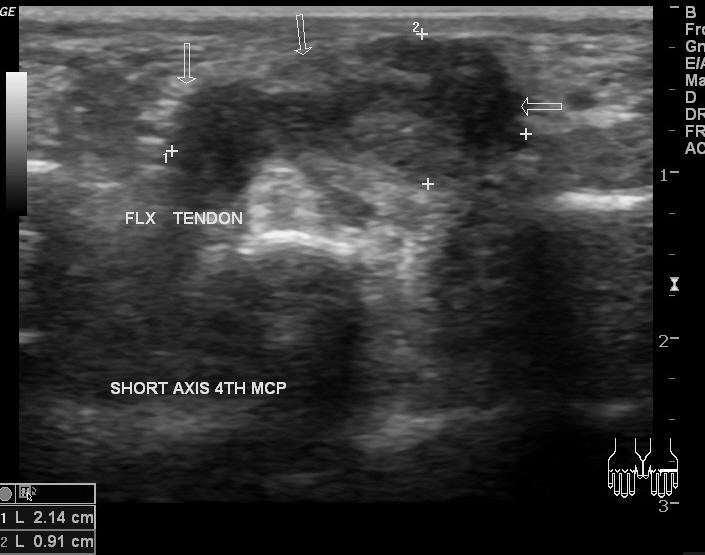

carpet layer

Baker's Cyst

2nd most common tumor of the hand and wrist

Giant Cell tumor (ganglion cyst)